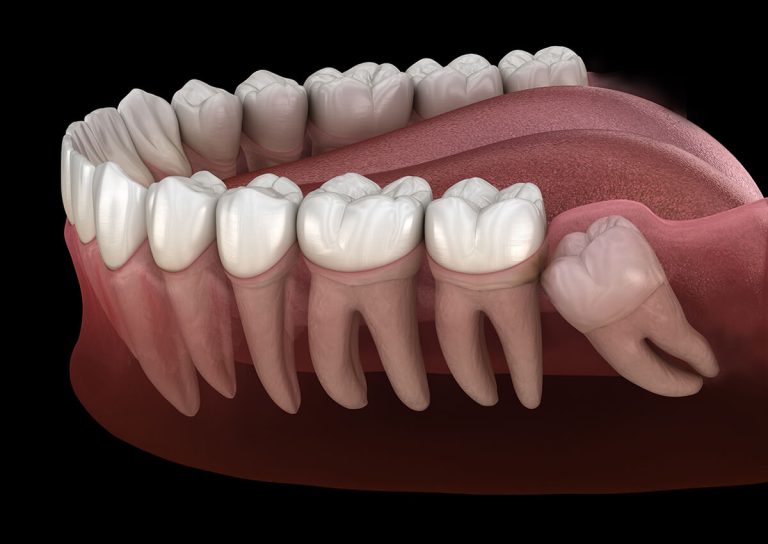

Having your wisdom teeth removed is a surgical procedure that requires proper aftercare to minimize discomfort, swelling, or infection. Following these instructions closely will help you heal faster and reduce the risk of complications.